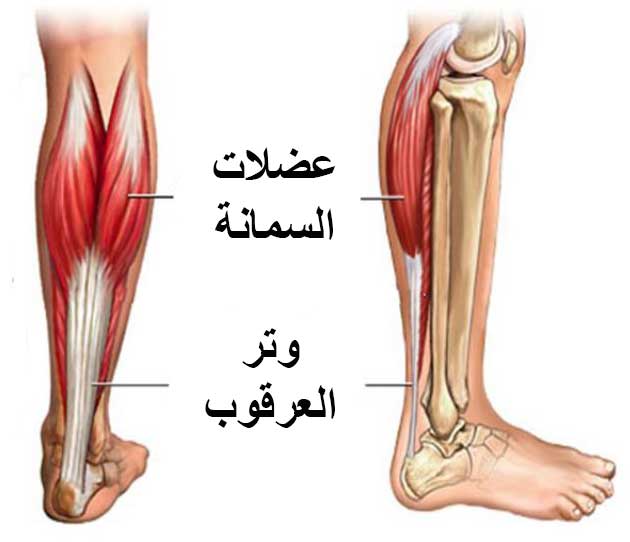

What is the Rotator Cuff? The rotator cuff is a group of muscles and tendons in the shoulder that connect the upper part of the arm (the humerus) to the shoulder blade (scapula). The tendons provide stability to the shoulder joint, while the muscles allow the shoulder to rotate.

- Tendonitis: It may result from continuous stress on the shoulder tendons, leading to their overuse and potential tearing due to excessive movement.

- Tendonitis: Tendonitis is one of the common causes of shoulder pain. It may result from minor tears or inflammation due to continuous stress on the shoulders, leading to pain and swelling in the affected area.

Torn Shoulder Muscles or Rotator Cuff: Injuries to the shoulder muscles or rotator cuff are common causes of neck and shoulder pain. Tears in these muscles can occur due to repeated stress or direct injury. Severe injuries may require surgical intervention, while less severe cases can be treated with physical therapy and pain-relieving medications.

Compression of the Rotator Cuff Tendons: Compression of the rotator cuff tendons in the shoulder can occur due to an improper sleeping position. This compression can result in shoulder pain upon waking up.

Rotator Cuff Tendonitis: Rotator cuff tendonitis is a common source of shoulder pain. It typically occurs in athletes who frequently raise their arms over their heads, such as swimmers, tennis players, and throwers. However, rotator cuff tendonitis can occur in anyone without a clear cause. Inflammation can cause pain and numbness in the shoulder, which may worsen after sleeping.